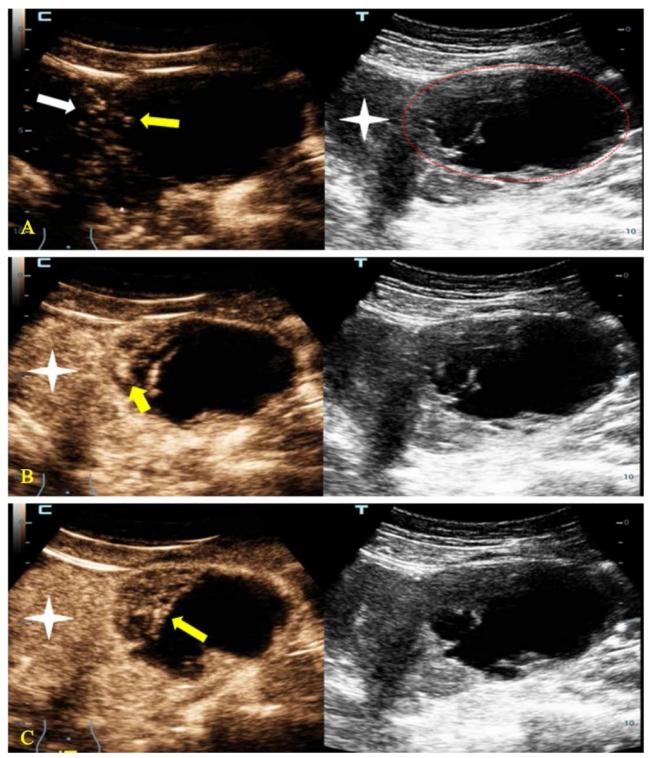

超声造影特征分别按如下标准进行赋分:肿块的造影剂到达时间早于或等于子宫肌层计2分,造影剂到达时间晚于子宫肌层计1分,肿块的增强强度高于或等于子宫肌层计2分,增强强度低于子宫肌层计1分,肿块在静脉期有快速消退计1分,共5分。当超声造影积分大于3分,O-RADS分类在原有基础上升1级(最高仍为5级),超声造影积分小于3分则降1级,积分等于3分则维持原来O-RADS分类不变。见图1

图1 一例35岁高级别卵巢囊腺癌患者的超声检查示例图

注:A~C中,左方为超声造影图,右方为同一平面的超声图。A图显示子宫左侧一个O-RADS 4类的囊实性肿块(红色线条区),超声造影图显示肿块内造影剂到达时间(黄色箭头)与子宫肌层造影剂到达时间(白色箭头)基本相同。B图显示动脉期肿块内部增强最强区域(黄色箭头)要高于子宫肌层(星号)。C图显示消退期肿块(黄色箭头)与子宫肌层(星号)相比有消退。该肿块因超声造影积分为5分而升级其风险分层至O-RADS 5类。

Figure 1 Example of ultrasound examination in a 35-year-old patient with high-grade ovarian cystadenocarcinoma

O-RADS超声分类是根据超声特征对卵巢附件肿块进行风险分层[12-13]。其极大方便了超声医师、临床医师和患者之间的沟通。这种风险分层的应用和验证也正在全球其他地区得到证实[10,14 -17]。卵巢癌的病死率居妇科恶性肿瘤之首,早期诊断对其治疗及预后有重要影响[18-20]。O-RADS分类对卵巢附件恶性肿块具有很高的诊断灵敏度,但随之而来的是低特异度。如本研究选取诊断恶性肿瘤的截断值为分类≥ O-RADS 4类,其灵敏度和特异度分别为0.966(95% CI为0.822~0.999)和0.361(95% CI为0.265~0.467),虽然灵敏度高可以避免恶性肿瘤的漏诊,但较低的特异度可能导致很多良性肿块被当成恶性肿瘤而过度治疗。超声造影的应用则有可能解决O-RADS分类对卵巢附件恶性肿块诊断特异性低的难题[21-27]。Yuan等[11]的研究中采用了一种独特的超声造影积分结合O-RADS分类的方式,这种结合提高了恶性肿块的诊断特异度。其将3个超声造影特征赋予不同分值,如肿块的造影剂到达时间早于或等于子宫肌层计2分,造影剂到达时间晚于子宫肌层计1分,肿块的增强强度高于或等于子宫肌层计2分,增强强度低于子宫肌层计1分,肿块在静脉期有快速消退计1分,总计共5分。当超声造影积分大于3分,O-RADS分类在原有基础上升一级(最高仍为5级),超声造影积分小于3分则降一级,积分等于3分则维持原来O-RADS分类不变。本研究采用结合超声造影积分和O-RADS分类的方法,如图1所示病例,造影前该卵巢附件肿块判定为O-RADS 4类,造影后肿块造影积分为5分,升级肿块风险分层至O-RADS 5类。本研究中,造影前O-RADS 4类肿块中共有15例恶性肿块和57例良性肿块,完成超声造影检查后计算积分,15例恶性肿块中的11例正确地升级到O-RADS 5类,而57例良性肿块中的33例正确地降级至O-RADS 3类。若同样选择预测恶性肿瘤的截断值分类≥ O-RADS 4类,其灵敏度和特异度分别为1.000(95% CI为0.881~1.000)和0.723(95% CI为0.622~0.811),这种结合超声造影和O-RADS分类的方法提高了卵巢附件恶性肿块的诊断特异度。